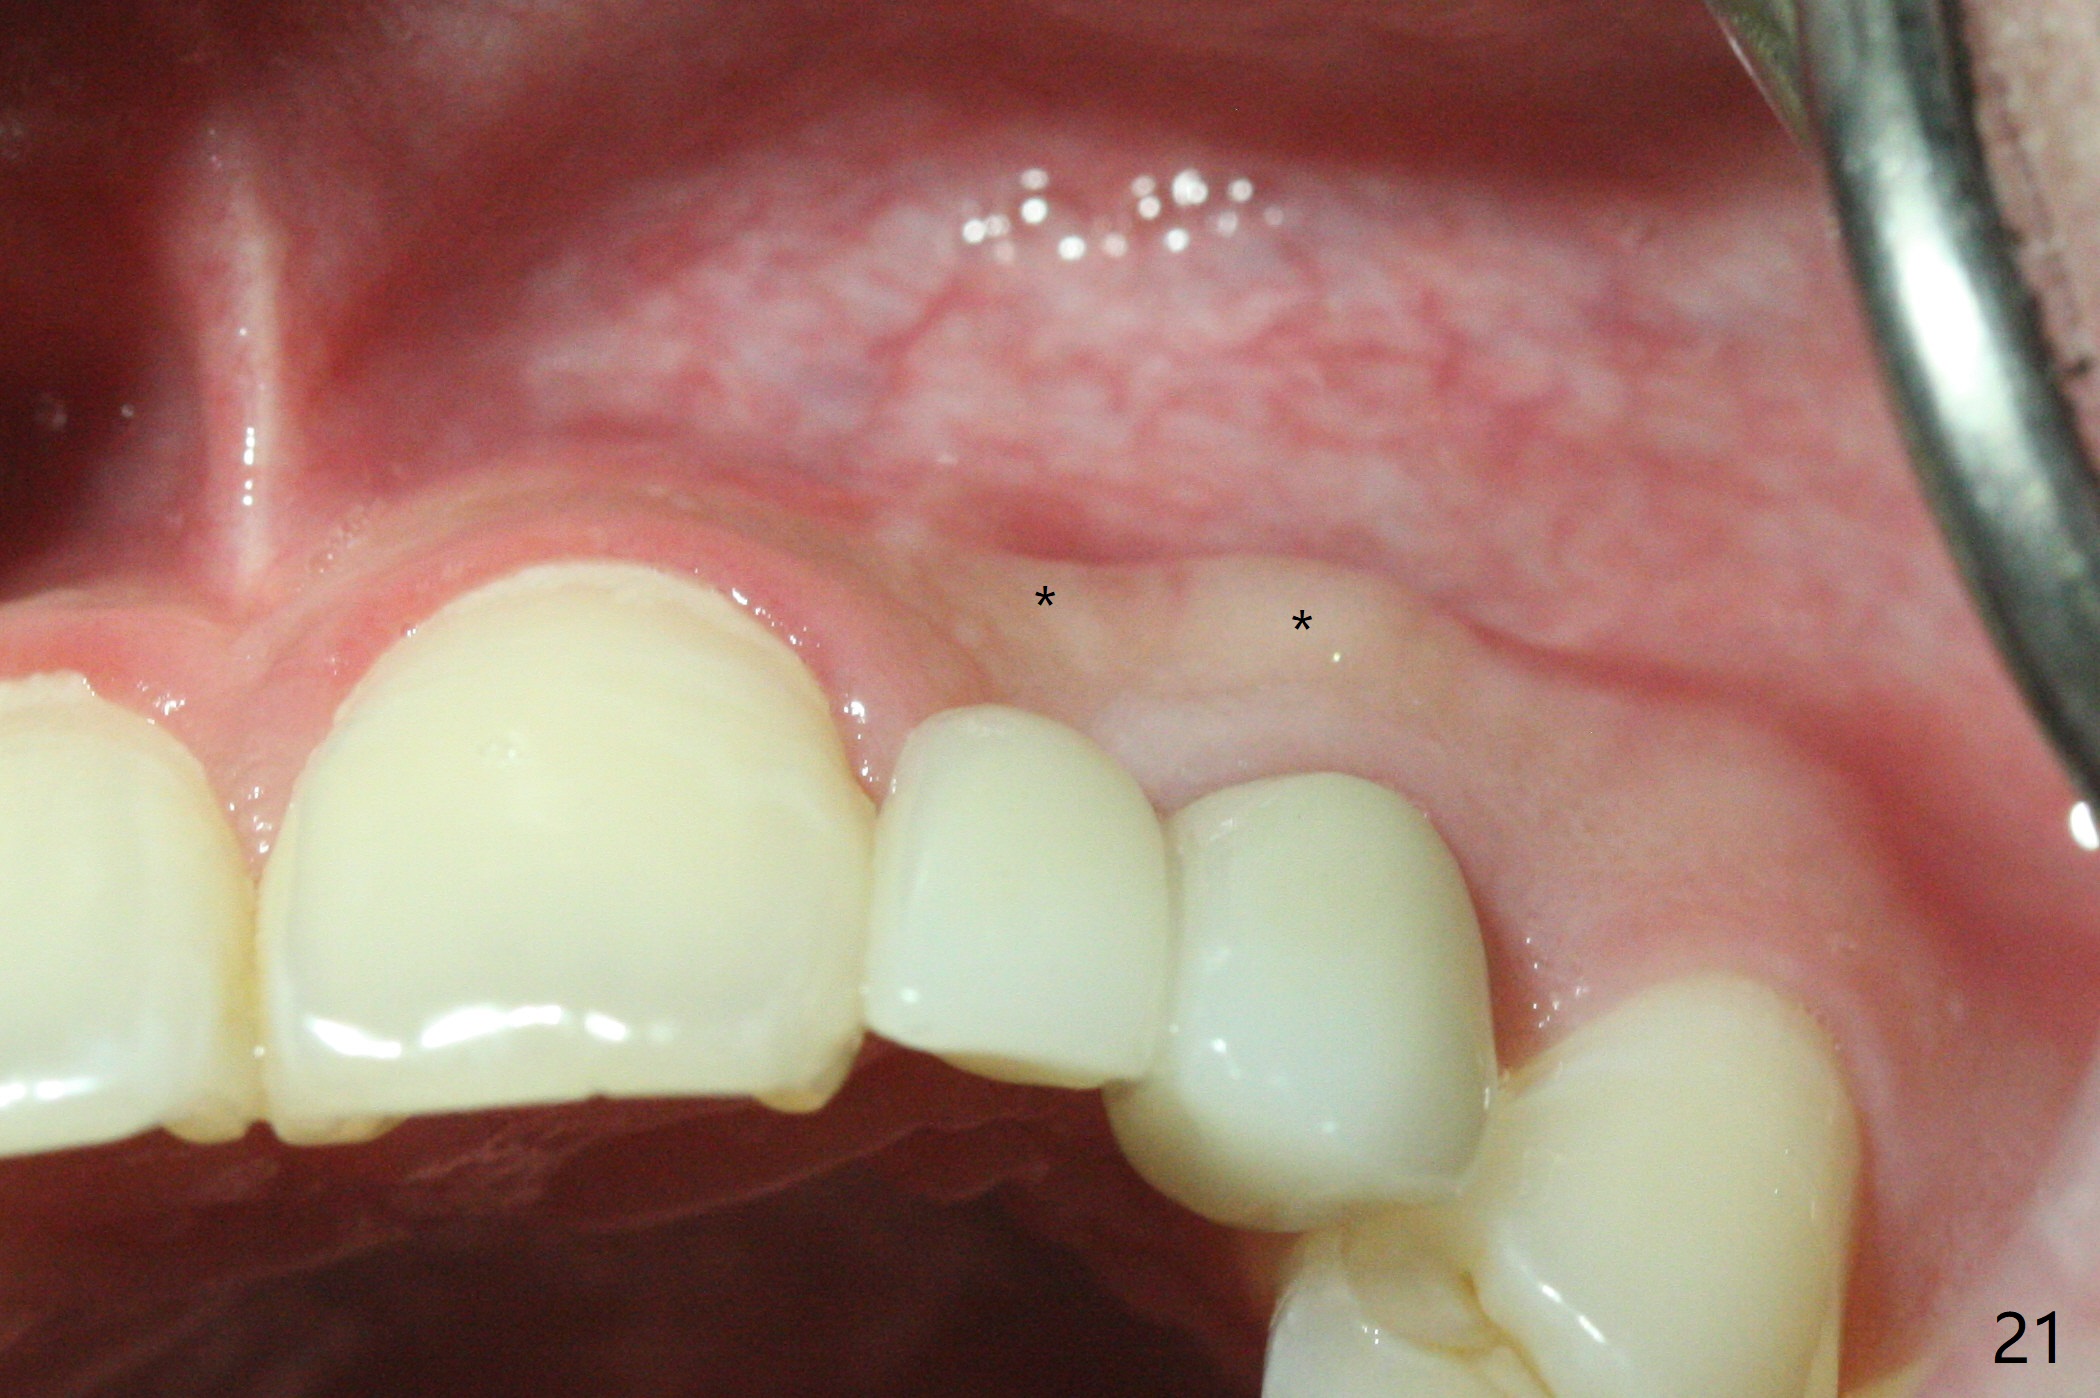

18岁男从外州大学回来,无症状,但是6号牙(右上尖牙)颊侧瘘道(图一,二(角化龈充分(箭头))),根尖片显示植体近中骨吸收(图三:*),而对侧植体仿佛骨整合(图四)。患侧切开后发现植体颊侧暴露,松动。拔除后骨缺损由粘性骨粉修复(图七,九:*),覆盖PRF膜(图七:P)和带钛网(图九:^)不可吸收膜(图五-七),后者用两个小钉子固定(图六(腭侧),七(颊侧),九),使用新的刀片和一个特殊尖头剥离器在颊侧骨膜下相当广泛分离,使用PTFE缝线,粘膜下水平褥式缝合之后(图八:箭头),多个垂直间断缝合,两个乳头垂直褥式缝合。术后一周伤口没有裂开,术后疼痛肿胀已经消退(图十)。术后十八天牙槽嵴仿佛比对侧还要宽(图十一,三与图十二,四(取模)对比)。术后5.5个月伤口没有裂开,牙槽骨,角化龈宽(图十六),与钛网和两个小钉子固定有关(图十五,十七)。CT显示牙槽骨只能容纳2.5或者3.0毫米植体(图十八)。11号牙植体牙冠粘固后没有骨质吸收(图十九),其实10,11号牙颊侧骨板隆起(图二十至二十二),而6植体失败,颊侧骨板吸收,甚至累及5号牙(图十七)。